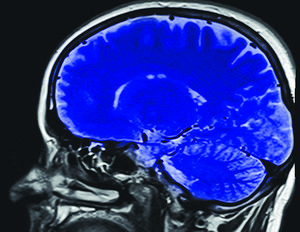

La esquizofrenia se manifestaría a raíz del "podado" neural de la adolescencia, donde el cerebro selecciona lo útil